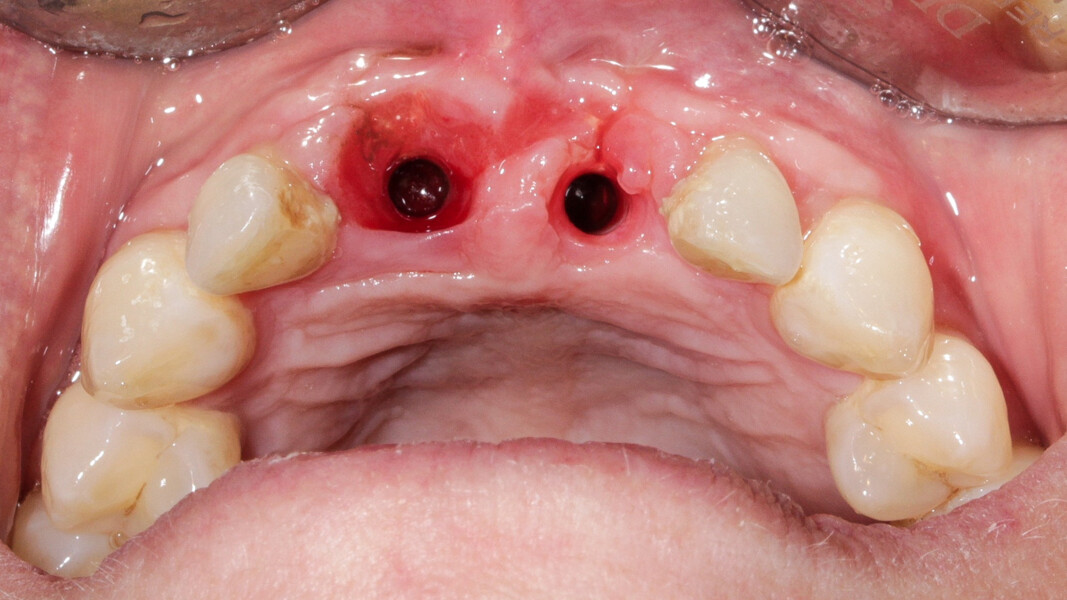

Une patiente de 49 ans nous a été adressée par l’un de nos confrères pour le remplacement de ses quatre incisives maxillaires (Fig. 23). Dans un contexte parodontal avancé, ses incisives centrales présentent une mobilité terminale (classe IV) elle n’ose plus les brosser de peur de les perdre lors de la manoeuvre. La patiente ne présente pas de problèmes de santé particuliers.

À l’examen, on observe une mobilité des quatre incisives maxillaires, une insuffisance osseuse verticale et horizontale, associées notamment au niveau de 11 et 21, la présence de plaque, de tartre et d’inflammation gingivale, surtout au niveau du bloc antérieur maxillaire. On note également la présence d’une dent de sagesse (dent 18) perdue (Figs. 24–26).